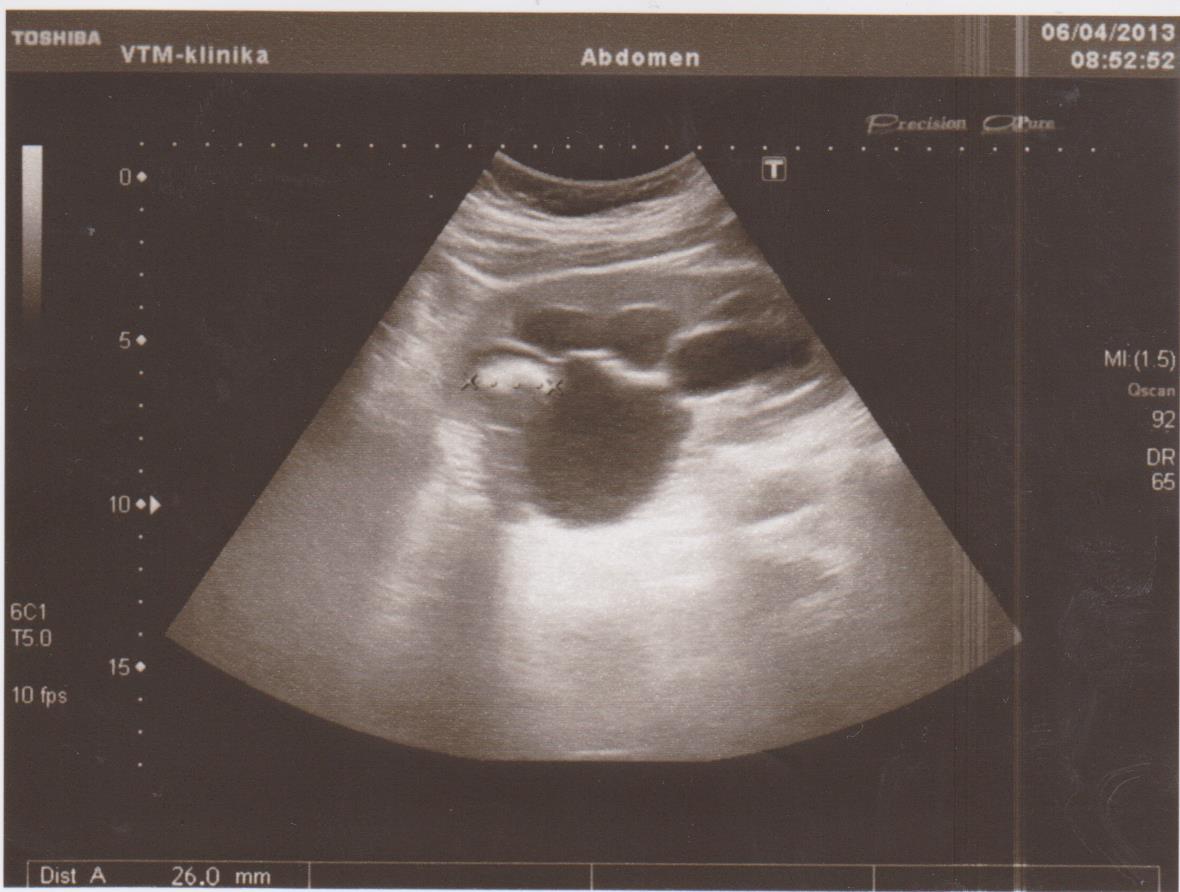

Частые болезни: кисты, новообразования (ангиомиолипомы, гемангиомы, фибромы…), конкременты (камни), расширение мочевых путей (расширение лоханки или чашечек — пиелоэктазия, гидронефроз), хроническое воспаление (пиелонефрит), смещение почек (опущение — нефроптоз, нахождение в нетипичном месте — дистопии), удвоение почки, рак почки…

Ниже я привел пару УЗИ снимков из практики, все они есть в галерее УЗИ на сайте, смотрите и не пугайтесь: